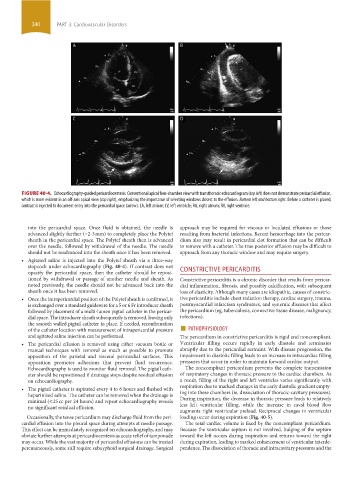

FIGURE 40-4. Echocardiography-guided pericardiocentesis. Conventional apical four-chamber view with transthoracic echocardiogram (top left) does not demonstrate pericardial effusion,

which is more evident in an off-axis apical view (top right), emphasizing the importance of selecting windows closest to the effusion. Bottom left and bottom right. Before a catheter is placed,

contrast is injected to document entry into the pericardial space (arrow). LA, left atrium; LV, left ventricle; RA, right atrium; RV, right ventricle.

• Agitated saline is injected into the Polytef sheath via a three-way

stopcock under echocardiography (Fig. 40-4). If contrast does not

opacify the pericardial space, then the catheter should be reposi- CONSTRICTIVE PERICARDITIS